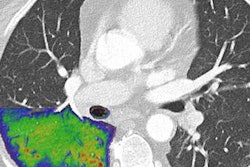

The investigators calculated "excess relative risk" of brain cancer per 100 mGy of cumulative brain radiation dose, reconstructing organ doses using historical machine settings and a thorough sample of CT images. Primary outcome for the study was first reported brain cancer five years after an individual had a first CT exam.